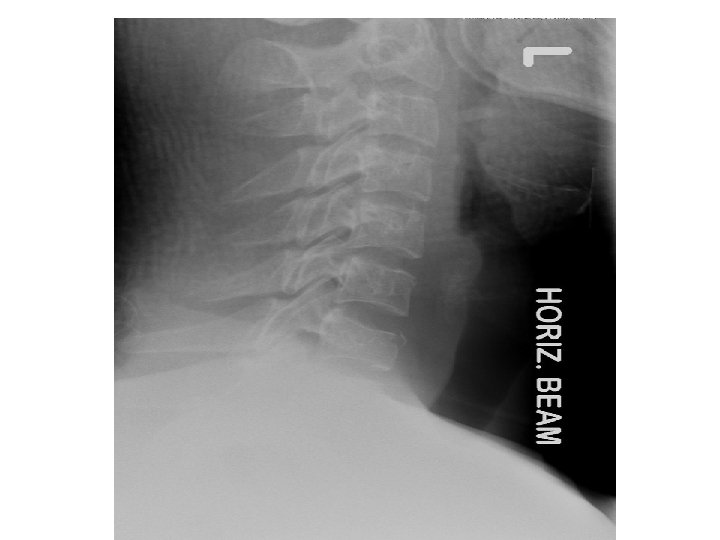

• • • Most important view Can see 80 -90% of injuries Interpretation: A - adequacy A - alignment B - bone C - cartilage D - disc S – soft tissue • • • A - Must have a view of C 7 – T 1 A - Use 3 lines 1. anterior vertebral line 2. posterior vertebral line 3. spino laminar line (base of spinous processes) 4 th line can be used ie. Tips of spinous processes •

• Check : • B - individual vertebrae • C - cartilage • D - disc • S - soft tissue • <7 mm at C 3 • <21 mm at C 7 • no more than vertebral body width at C 7 • Predental space – • 5 mm child • 3 mm adult • Fanning of spinous processes